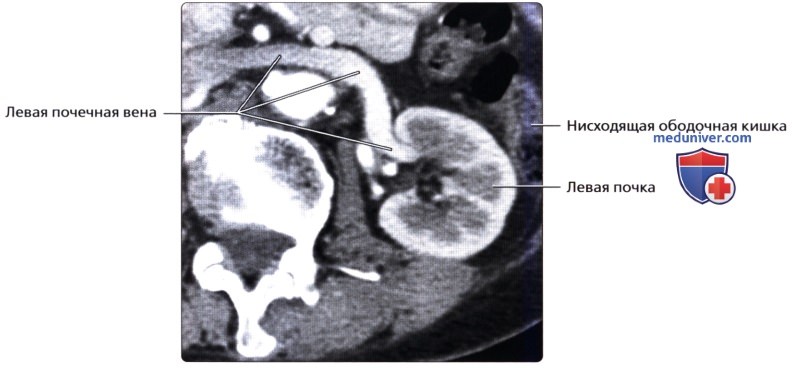

а) Анатомия почек:

2. Топографическая анатомия почки:

• Лежат в забрюшинном пространстве, окружены почечной фасцией (фасция Героты)

• У взрослого каждая почка около 9-14 см в длину и 5 см в ширину

• Обе почки лежат «на» квадратных мышцах поясницы, латеральнее поясничных мышц

3. Внутренняя структура:

• Почки можно рассматривать как полый орган, просвет которого занят жировой тканью, почечной лоханкой, чашечками, сосудами и нервами

• Ворота почки: сюда подходят артерия и вена и выходит мочеточник

• Почечная лоханка: расширение верхнего конца мочеточника в виде воронки:

о Собирает мочу от больших чашечек (2 или 3), каждая из которых в свою очередь собирает мочу от малых чашечек (2-4)

• Почечный сосочек: точечная верхушка почечной пирамиды, содержащей собирательные трубочки, выделяющие мочу

о Каждый сосочек открывается в малую чашечку

• Корковое вещество почки: периферическая часть, содержит почечные (клубочки, сосуды), проксимальные части собирательных трубочек и петли Генле

• Мозговое вещество почки: внутренняя часть, содержит почечные пирамиды, дистальные части собирательных трубочек и петли Генле

• Кровеносные и лимфатические сосуды, нервы:

о Артерия:

— Обычно по одной к каждой почке

— Отходит от аорты на уровне L1-L2 позвонков

о Вена:

— Обычно по одной от каждой почки

— Лежит кпереди от почечной артерии и почечной лоханки

б) Лучевая анатомия почки:

1. Обзор:

• Забрюшинные структуры бобовидной формы с четким контуром, смещающиеся при дыхании

• Почечные вены:

о Лучше всего визуализируются при поперечном трансабдоминальном сканировании

о Также могут быть видны при сканировании в фронтальной плоскости с заднебоковой поверхности